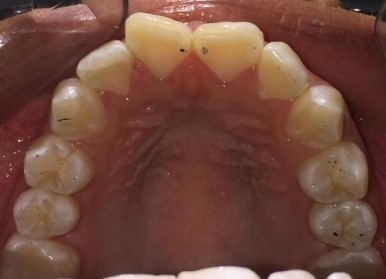

Commentaires

- Elastiques de réduction interproximale et Classe II pour la correction de canine de classe II

- Dérotation et rétraction des incisives maxillaires

- Forme d'arcade ovale

- L'expansion molaire supérieure et les taquets multi-plans optimisés pour la rotation de la deuxième molaire inférieure ont été utilisés pour la résolution de l'occlusion croisée postérieure gauche

État initial